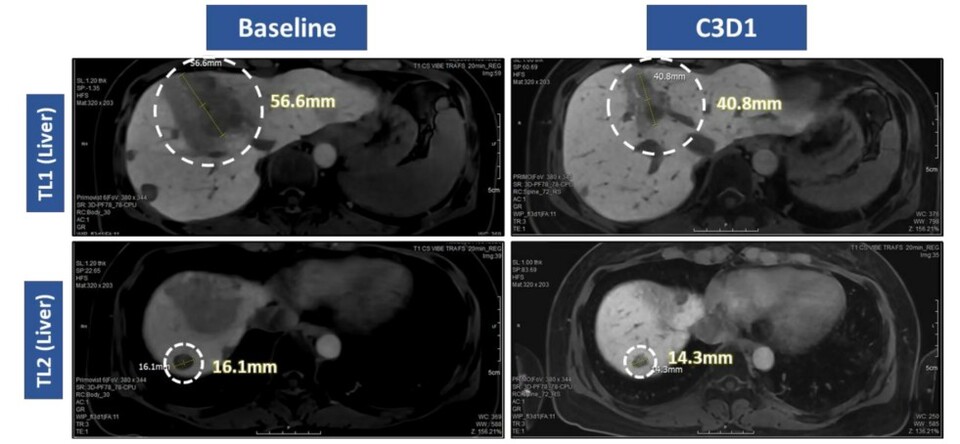

이번 발표에 따르면 VRN10은 초기 용량임에도 불구하고 괄목할 만한 ‘항종양 효과’를 보였다. 80~160㎎까지의 초기 투약군 환자 중 3명에서 종양 감소가 확인됐고, 그중 1명은 종양 크기가 30% 이상 줄어드는 ‘부분관해(PR)’를 달성했다.

특히 ‘엔허투(Enhertu, 성분 트라스투주맙 데룩스테칸)’를 포함한 기존 치료제에 불응하고 종양이 진행된 강원 랜드 바카라 변이 유방암 환자에서도 30% 수준의 종양 감소를 보여 폭넓은 치료 가능성을 입증했다고 회사는 강조했다.